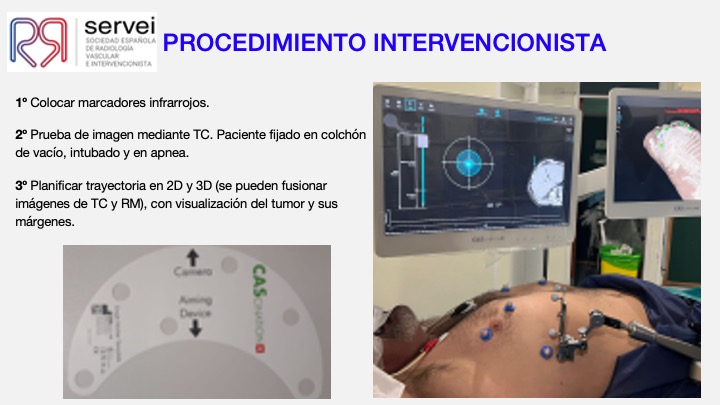

- Ablacion estereoataxia lesiones hepaticas 01

- Ablacion estereoataxia lesiones hepaticas 02

- Ablacion estereoataxia lesiones hepaticas 03

- Ablacion estereoataxia lesiones hepaticas 04

- Ablacion estereoataxia lesiones hepaticas 05

- Ablacion estereoataxia lesiones hepaticas 06

- Ablacion estereoataxia lesiones hepaticas 07

- Ablacion estereoataxia lesiones hepaticas 08

- Ablacion estereoataxia lesiones hepaticas 09

- Ablacion estereoataxia lesiones hepaticas 10

- Ablacion estereoataxia lesiones hepaticas 11

- Ablacion estereoataxia lesiones hepaticas 12

- Ablacion estereoataxia lesiones hepaticas 13

- Ablacion estereoataxia lesiones hepaticas 14